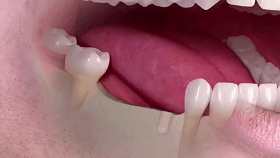

牙齿缺失会引起邻牙松动、对牙伸长、引发牙周病,最终牙齿脱落等一系列问题,还会因咬合紊乱致使面容苍老、咀嚼功能变差引发肠胃疾病,甚至影响身体健康。

种植牙是医学界公认的理想修复方式,被誉为“人类的第三副牙”。相比活动假牙不舒服、难清洗、容易引起口腔黏膜病变,种植牙更稳固耐用,舒适美观,咀嚼功能好,一次种植,终生受用。种植牙不仅是中老年人的专利,年轻人因意外、牙病等造成牙齿缺失,也能够通过种植牙进行修复治疗,重获美丽笑容。